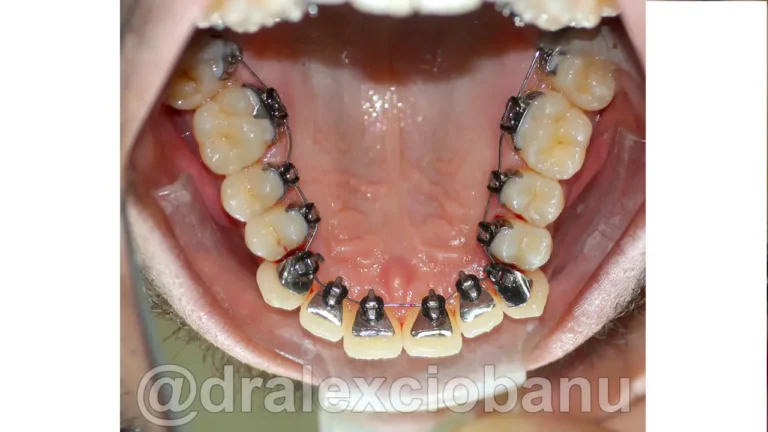

Il paziente presentava una malocclusione di prima classe per grave affollamento dentario superiore ed inferiore.

Al fine di garantire un alto livello di estetica e precisione maggiore nello spostamento dei denti, sono stati applicati degli attacchi linguali 3D WIN LINGUAL SYSTEM in entrambe le arrecate.

I brackets linguali possono allineare sia le corone che le radici dei denti, in modo che siano perfettamente posizionati l’uno accanto all’altro in posizione corretta. È spesso difficile ottenere questo posizionamento utilizzando gli allineatori rimovibili, specialmente quando si tratta di correggere le rotazioni dei canini. I brackets linguali fissi possono posizionare perfettamente i canini e i denti anteriori nella posizione corretta, come mostrato nella radiografia orto panoramica al termine della terapia.